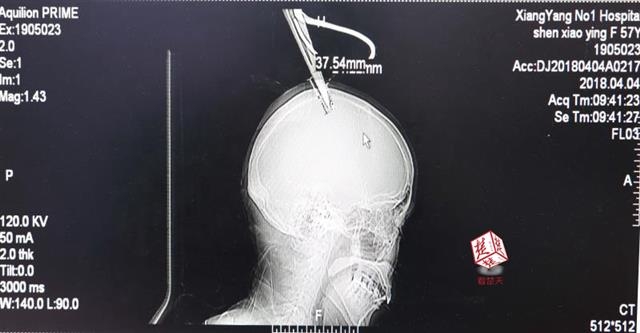

女子顱骨插進(jìn)剪刀 不慌不忙坐公交車就醫(yī)

醫(yī)生檢查發(fā)現(xiàn),剪刀刀尖斜嵌在沈某顱骨里,離腦髓只有兩三毫米。所幸是斜著插進(jìn)去,如果是垂直刺入,很有可能造成癱瘓。

4月4日清晨,襄陽市樊城區(qū)太平店鎮(zhèn)57歲的農(nóng)村婦女沈某,在采摘香椿嫩芽時(shí),綁在竹桿上的剪刀因竹子腐朽不慎折斷,剪刀斜插入頭顱。經(jīng)過及時(shí)搶救,目前脫離生命危險(xiǎn)。

“當(dāng)時(shí)感覺還好,就是頭有點(diǎn)木。”沈某說,由于自己感覺沒什么大礙,便沒坐120急救車,而是和家人一起坐了一個(gè)小時(shí)的公交車趕到市區(qū)醫(yī)院。

醫(yī)生檢查發(fā)現(xiàn),剪刀刀尖斜嵌在沈某顱骨里,離腦髓只有兩三毫米。所幸是斜著插進(jìn)去,如果是垂直刺入,很有可能造成癱瘓。最終經(jīng)過手術(shù),剪刀被取出,沈某目前仍在ICU進(jìn)一步觀察。